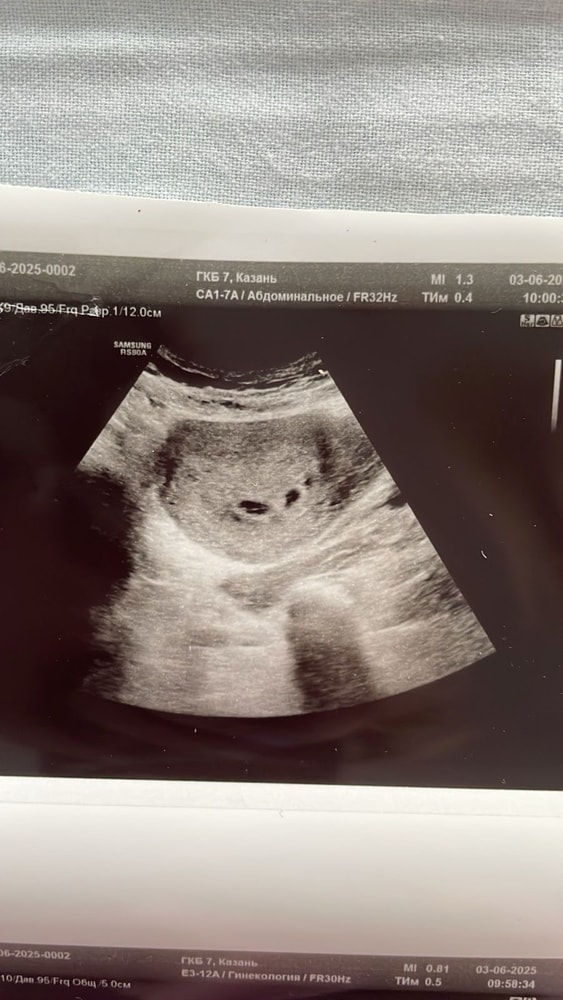

Больше вам скажу у меня не видели эмбрион при 6800 хгч, и даже 19000 😂 хотели почитстить,я писала отказ) и вот уже 8 недель,а у моего «пустого» пя чсс 178☺️ Изображение Но у меня в начале было подозрение на двойню,возможно поэтому хгч так рос Изображение